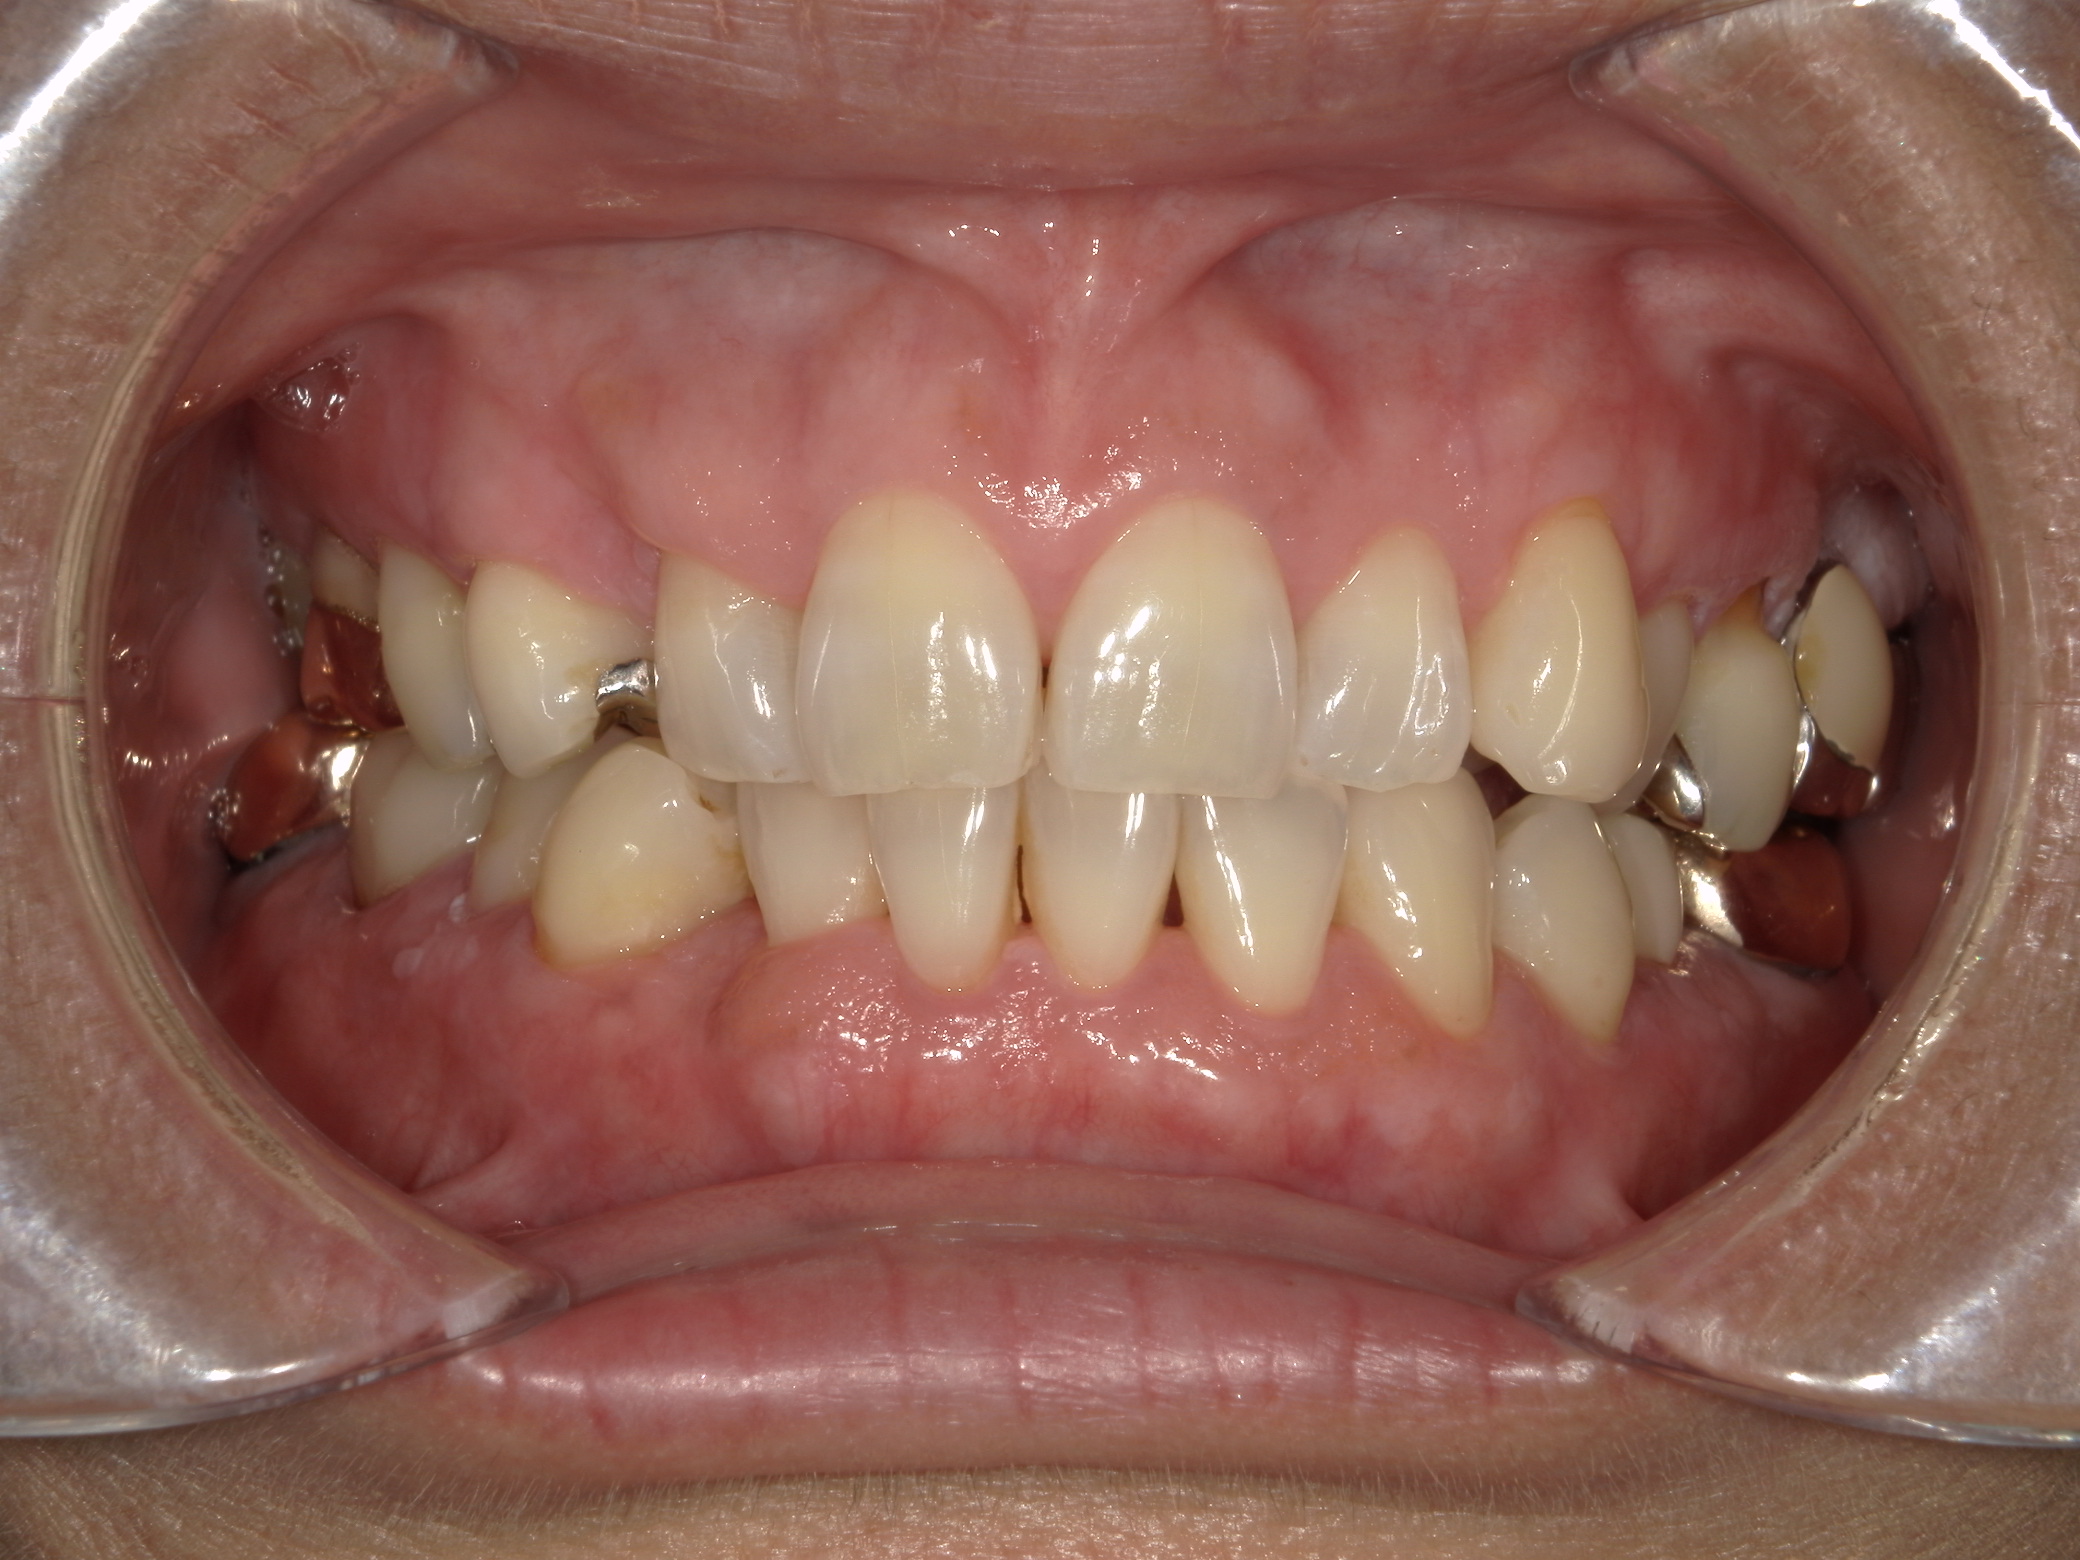

治療前

治療後